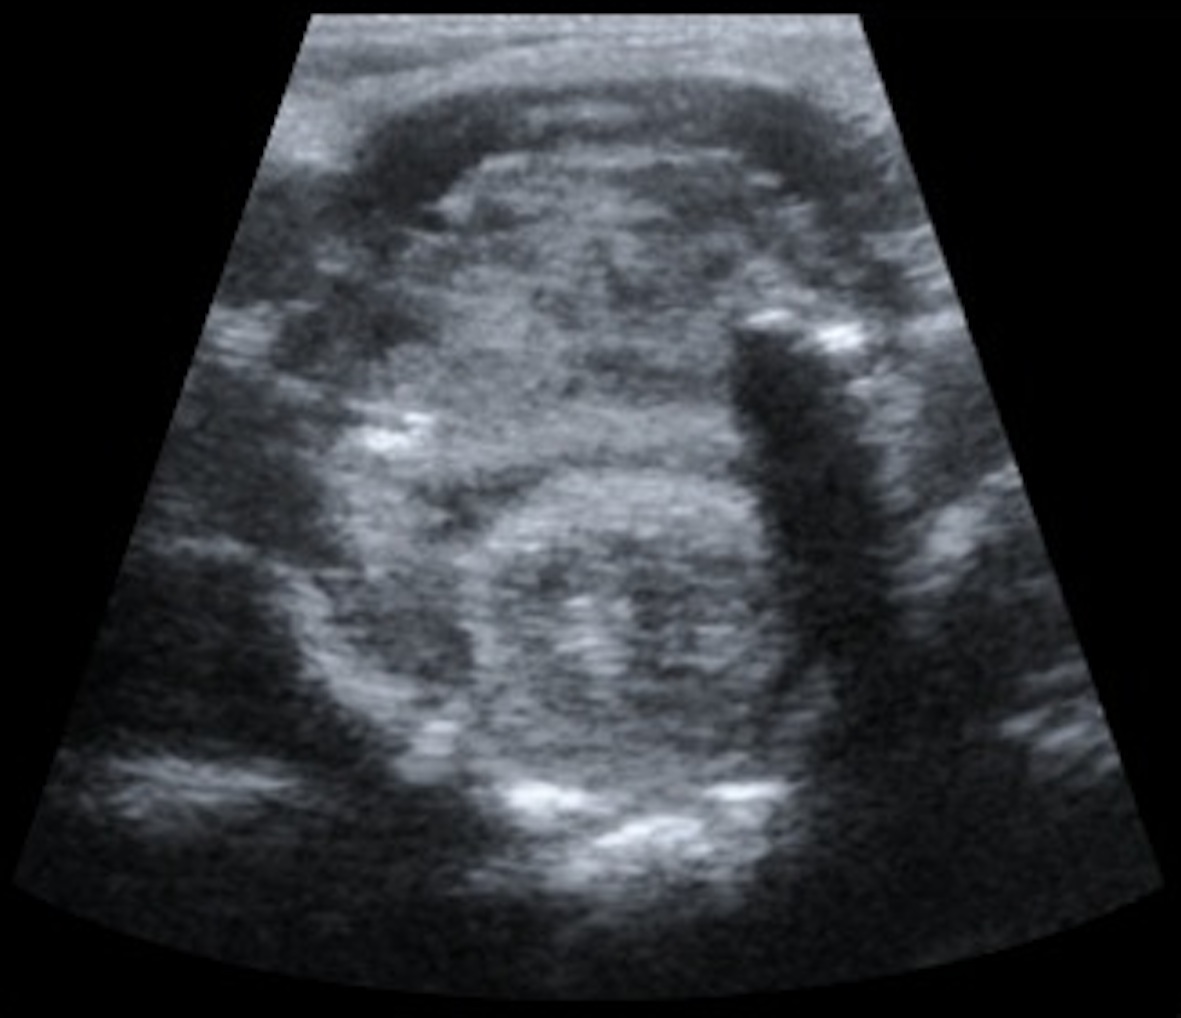

Pharyngeal hairy polyps are rare lesions that arise from the nasopharynx or oropharynx. It occurs predominately in females, with predilection for the left side. Its etiology remains poorly understood. It typically presents in the neonatal period with respiratory distress and feeding difficulties. Imaging is fundamental to identify the high fat content of the lesion. Surgical resection is the treatment of choice. We report a case of a nasopharyngeal hairy polyp causing respiratory distress since birth.